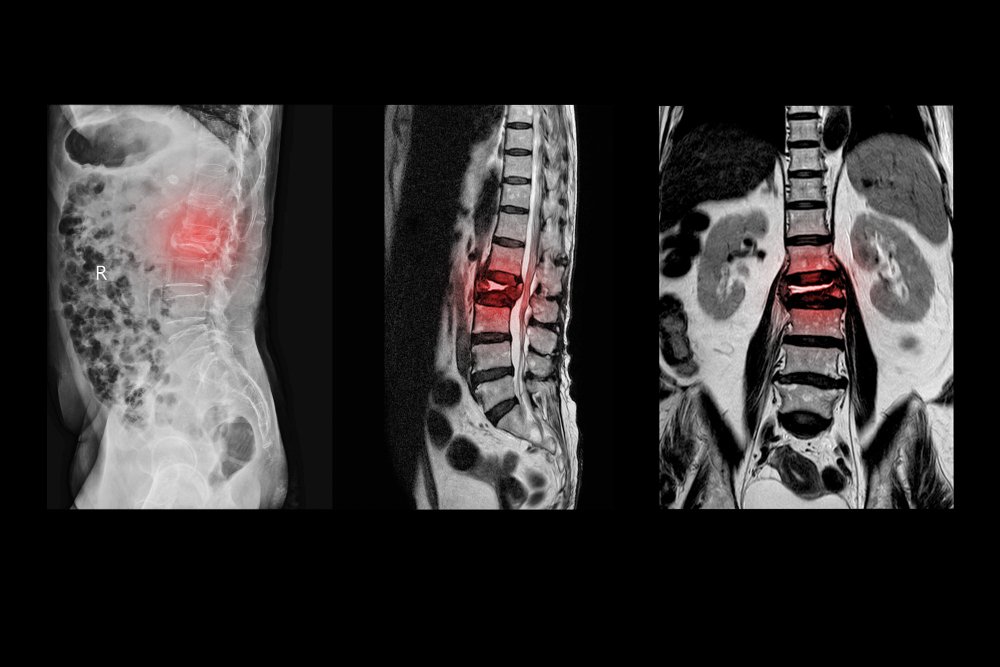

عادةً ما يكون التصوير بالرنين المغناطيسي هو الخيار الأفضل لفحص العمود الفقري. يتميز بقدرته الفائقة على تصوير الأنسجة الرخوة مثل الأقراص الغضروفية والأعصاب.

يتفوق هذا النوع من التصوير في تشخيص الانزلاقات الغضروفية والتهابات الأنسجة. كما يظهر بوضوح تمزق الأربطة والأوتار وضغط الأعصاب.

تتميز تقنية mri scan بقدرتها الفائقة على تصوير الأنسجة الرخوة داخل body. تظهر images مفصلة للأقراص الغضروفية وspinal cord والأعصاب المحيطة.

تكون التقنية الثانية أفضل في تصوير العظام والكسور. بينما يتفوق mri في كشف الانزلاقات وضغط الأعصاب المسببة لpain في back.

يظل mri الخيار المفضل للحالات المزمنة. يتميز بقدرته الفائقة على تصوير الأنسجة الرخوة وspinal cord والأعصاب المحيطة. هذا يساعد في تشخيص دقيق لمشاكل back.